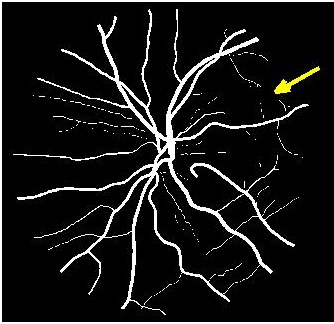

Results of fold cross validation for are presented in Table 1. Due to space constraints only SSIM values are shown for . For , performance difference of all methods is small but becomes more pronounced for higher . gives the best results for all , and the improvement over competing methods is significant as is evident from the values of Wilcoxon signed-rank tests. Figure 3 shows results of the top methods (due to space constraints) for . shows the best performance as is evident from the SR image in Fig. 3 (b) where one of the minor retinal branches (indicated by yellow arrow) is clearly visible. On the other hand the SR image by (Fig. 3 (c)) is blurry and does not clearly show this retinal branch. Other methods perform much worse, with significant blur visible for the main branches as well. Clearly, gives the closest reconstruction to the HR image of Fig. 3 (a).

![]() |

| (a) | (b) | (c) | (d) |